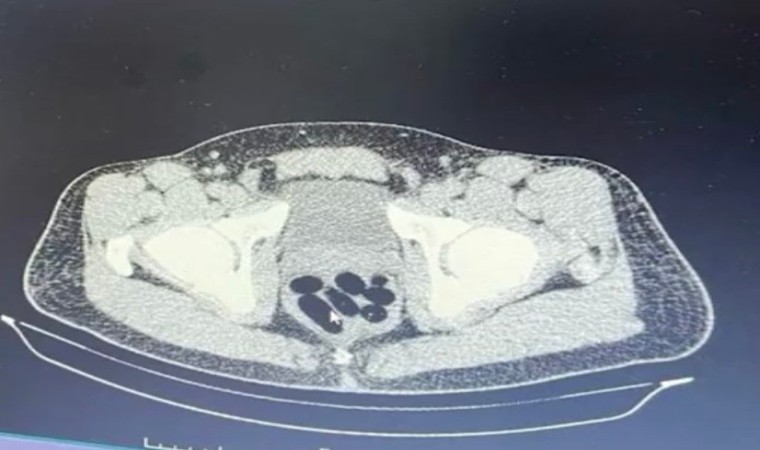

Kayseri İl Emniyet Müdürlüğü Narkotik Suçlarla Mücadele Şube Müdürlüğü ekipleri, uyuşturucu madde ticareti yapan şahıslara yönelik analiz çalışması yürüttü. M.R.B’nin (23) kente uyuşturucu madde getireceğini tespit eden ekipler operasyon düzenledi. Gözaltına alınan şahsın hastanedeki iç beden muayenesinde 77 adet kapsül şeklinde 1 kilo 134 gram narkotik madde ele geçirildi. Şahsın midesindeki maddeler cerrahi müdahale ile çıkarılırken, şahıs hakkında "uyuşturucu madde ticareti yapmak" suçundan adli işlem başlatıldı.